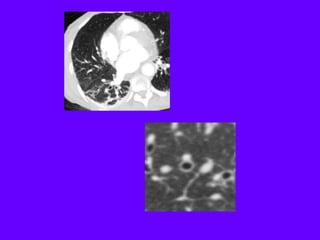

Cystic lung disease

Langerhans cell histiocytosis

Lymphangiomyomatosis complicated by pneumothorax

Lymphangioleiomyomatosis

HRCT Morphology

Thin-walled cysts (2mm - 5cm)

Uniform in size / rarely confluent

Homogeneous distribution

Chylous pleural effusion

Lymphadenopathy

in young women

Lymphangioleiomyomatosis (LAM)

Tuberous Sclerosis (young man)